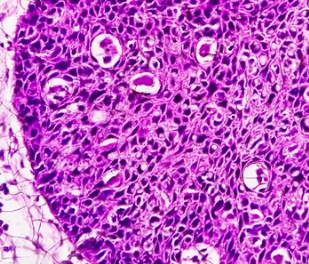

- 조직 검사: 구강 검진에서 암 의심 부위가 발견되면 조직 검사를 시행합니다. 혀의 일부를 떼어내 현미경으로 검사하여 암세포 유무를 확인합니다. 조직 검사는 혀암 확진에 필수적인 검사입니다.